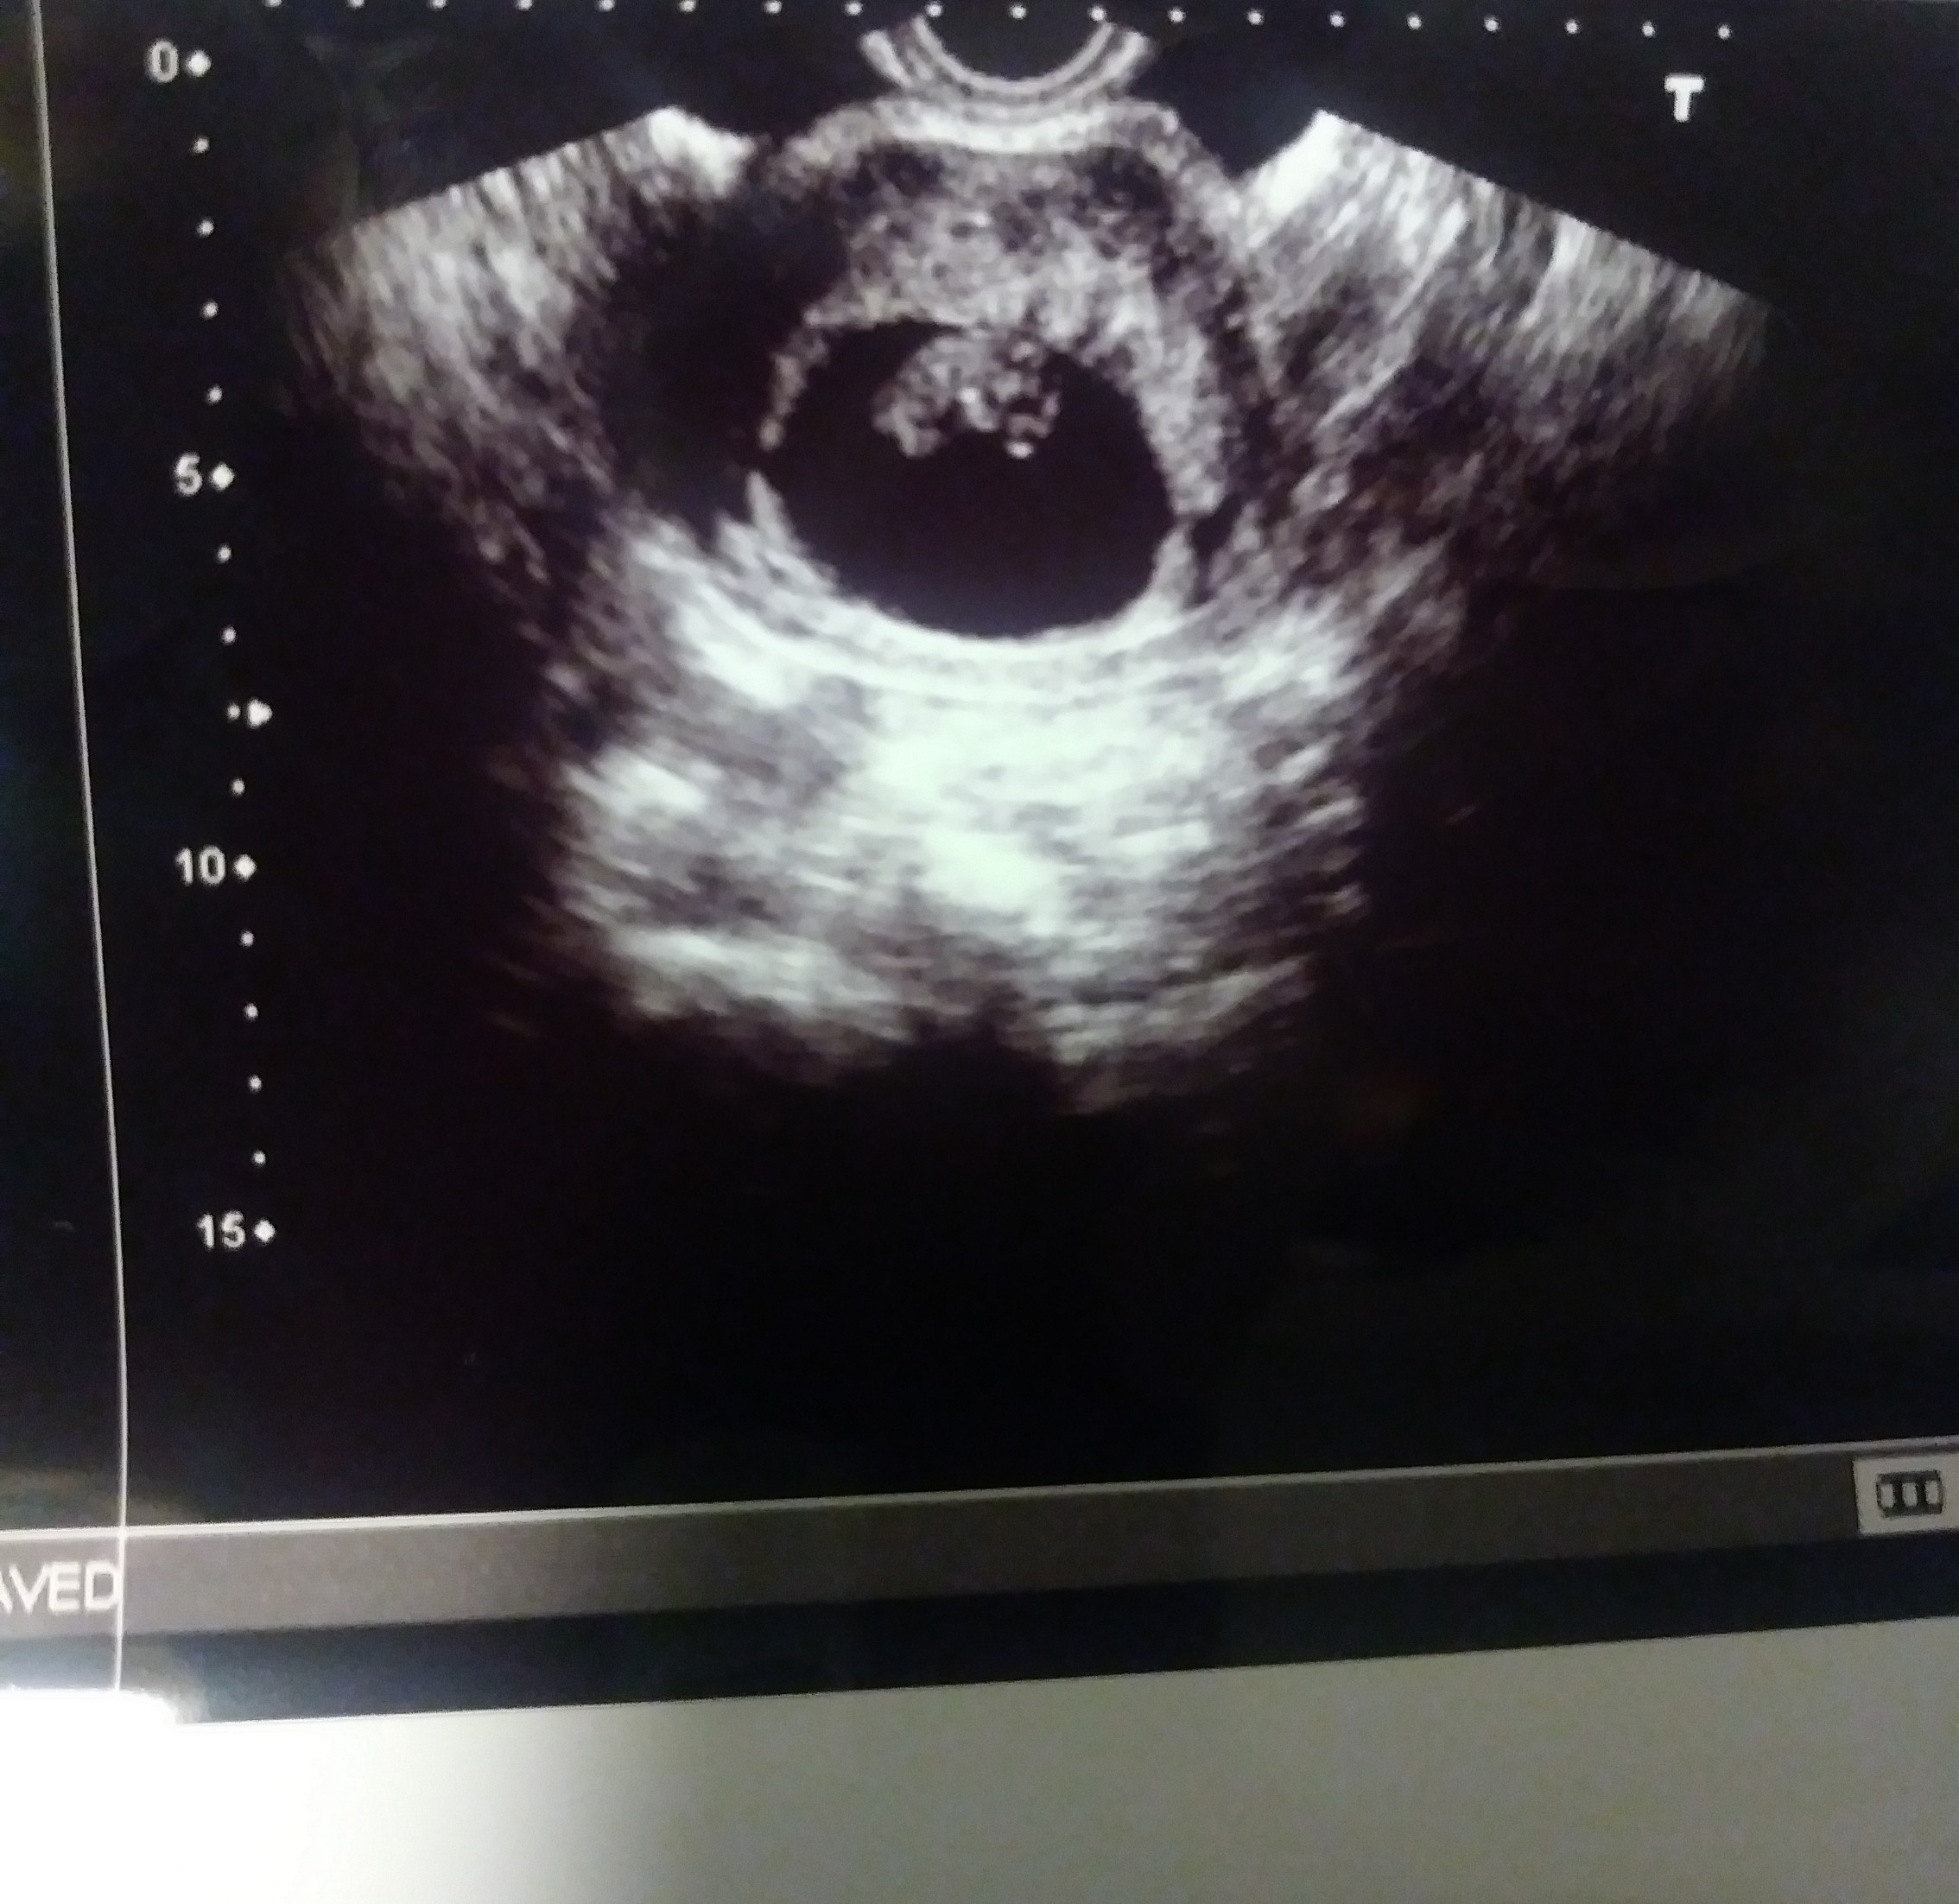

I'm 9 weeks and 5 days I had a vaginal ultrasound. Any guesses based on the ramzi theory?Attachment 37477

Ramzi theory is meant to be used for pregnancies between 6 and 7 weeks. It's been debunked anyway. It's also impossible to tell what angle the tech took this picture.